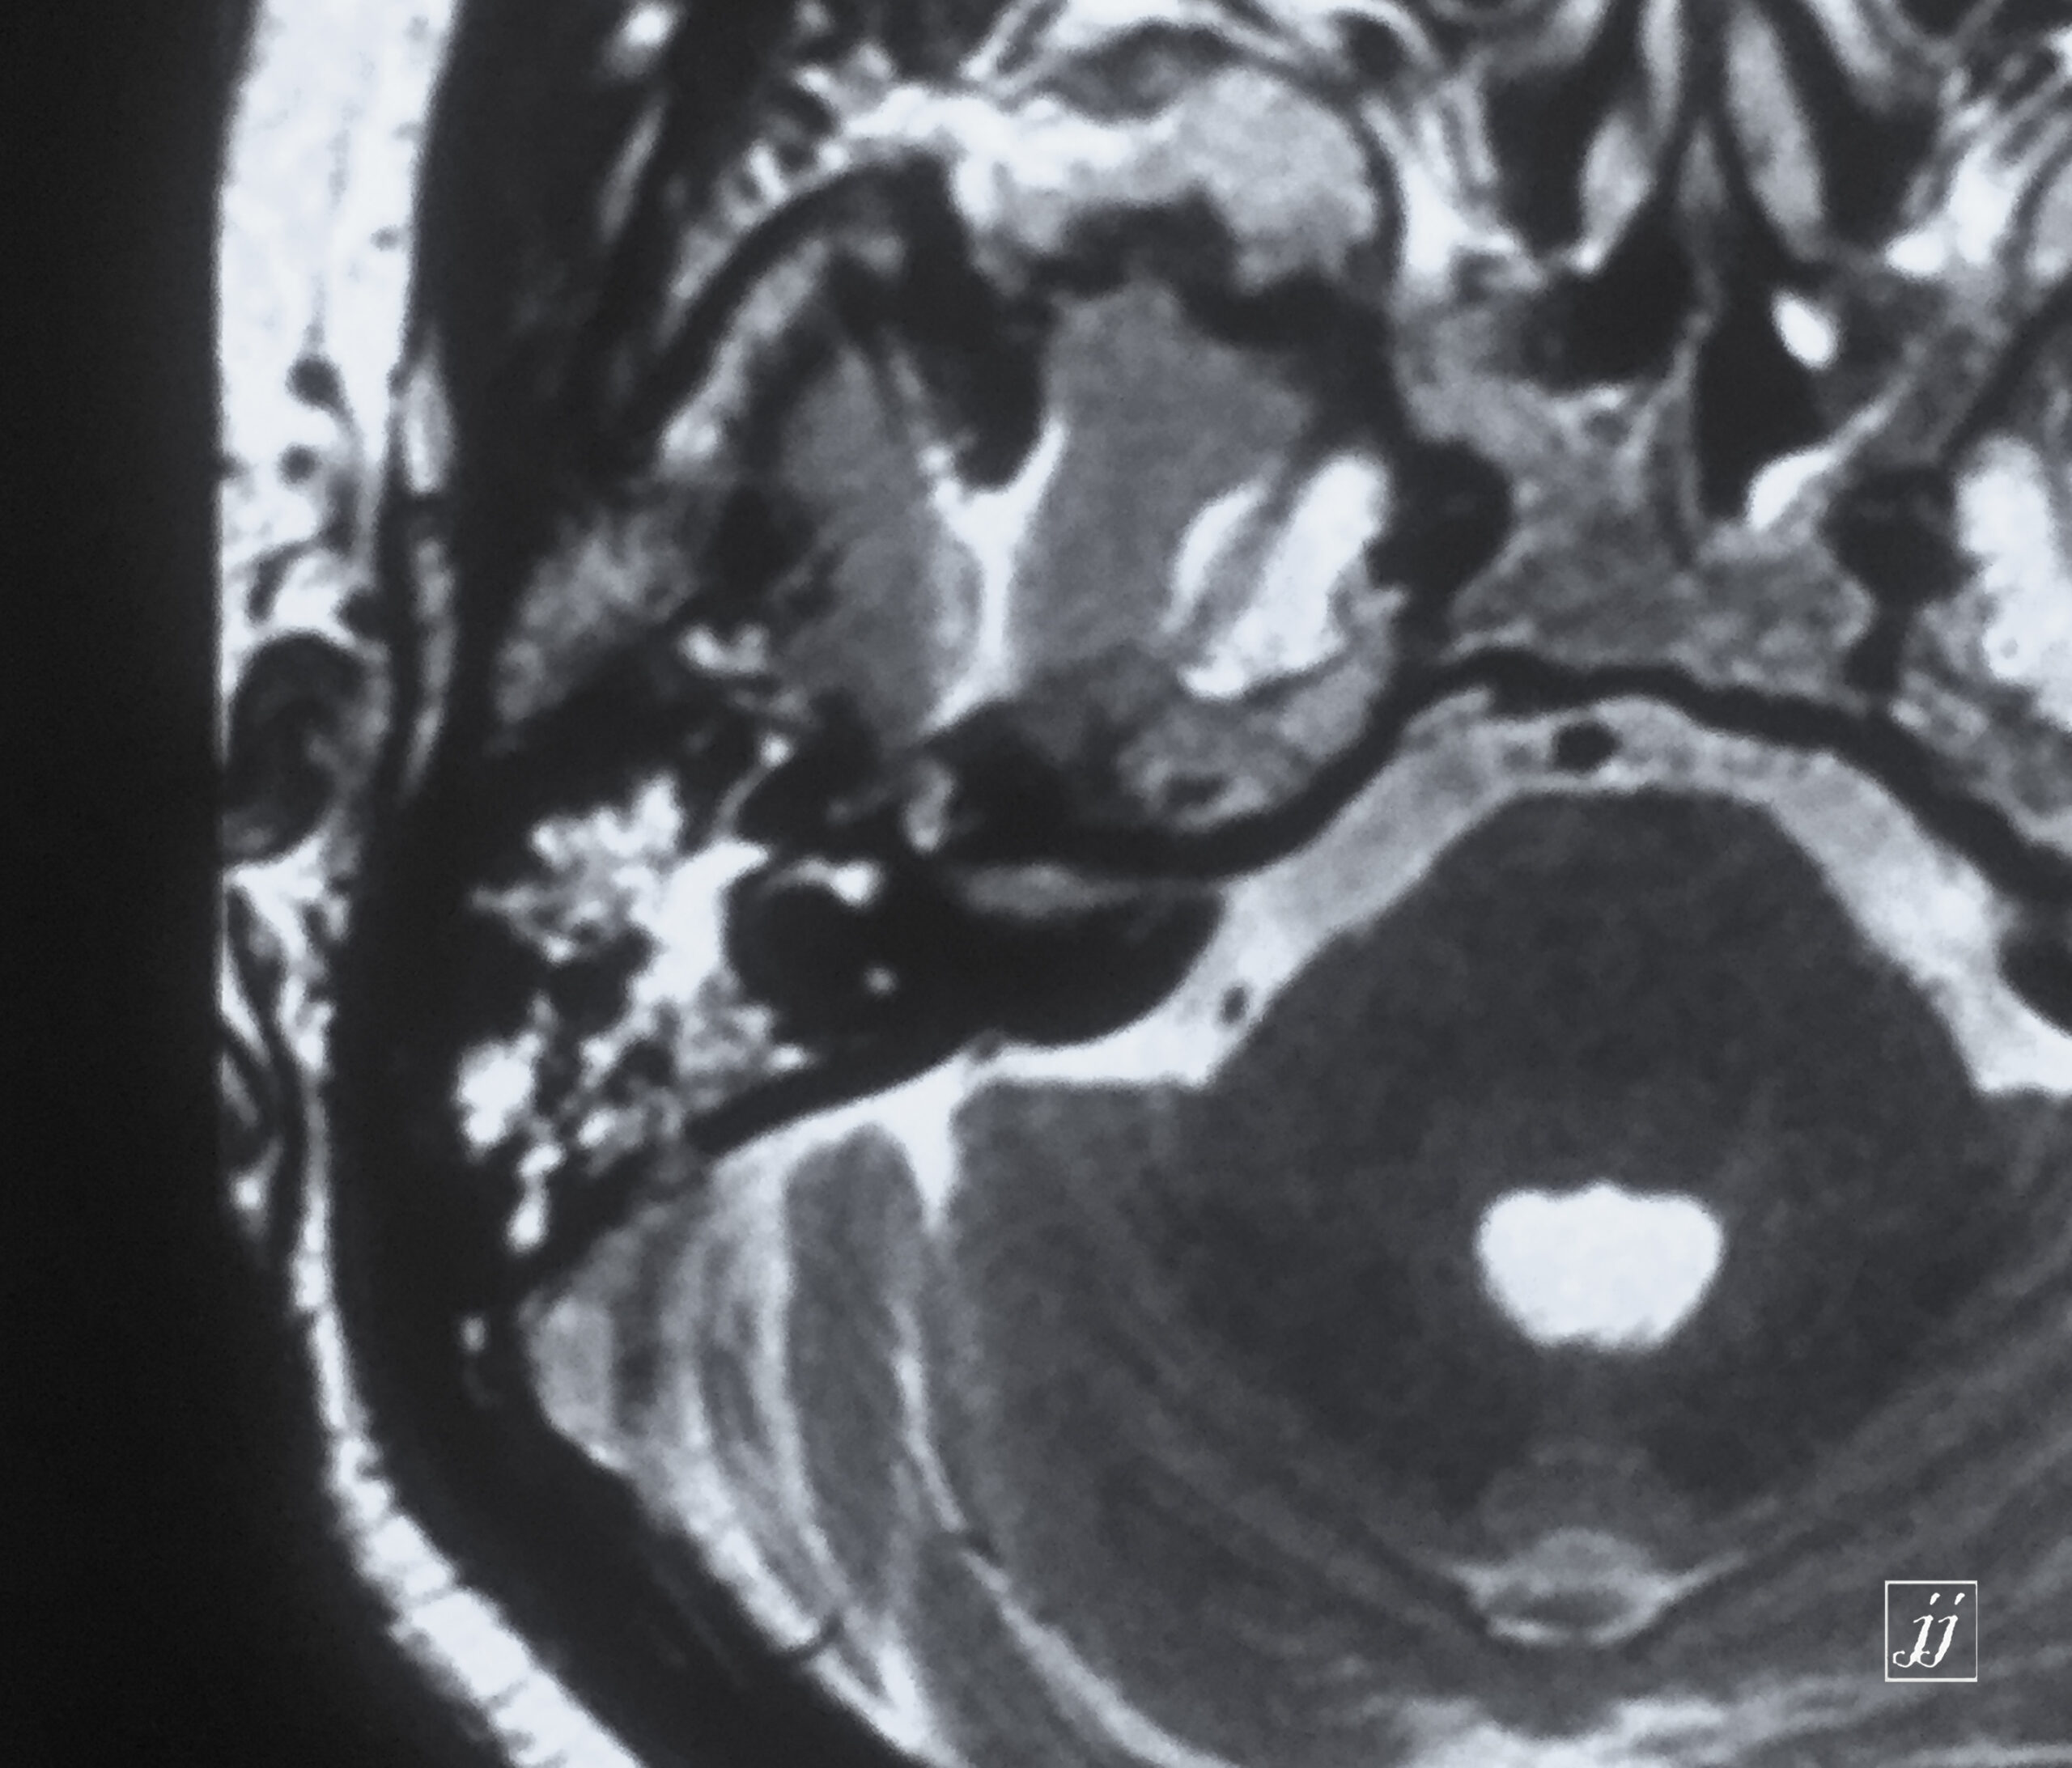

Brain- left glomus jugulars tumor (10)